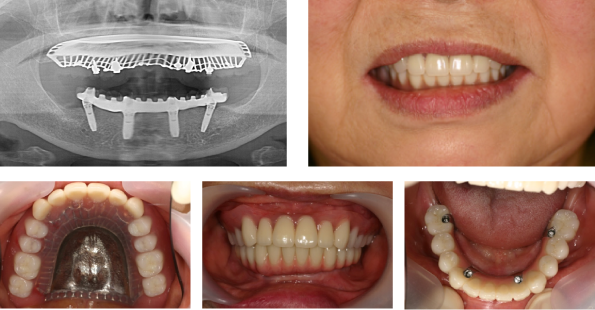

オールオン4(All on 4®︎)は、総入れ歯をお使いの方や多くの歯をなくした方に、最小4本のインプラントで12本の連結した歯を手術当日に装着し、速やかに見た目と噛み合わせ機能を回復する治療法です。

All on 4®︎では、前歯のあたりにインプラントを埋め込みます。奥のインプラントを骨のある前歯付近へ斜めに埋め込み、4本~6本のインプラントですべての人工の歯を支えることができます。前歯付近は太い神経や血管がないため、手術で神経や血管を傷つける心配がありません。また、ほとんどの場合は骨が残っているために、手術が可能です。

All on 4®は人工歯の色や形、質感を統一できるため、優れた審美性を実現します。美しい歯並びが得られることにより、患者様の自信も向上するでしょう。

従来のインプラントオペの考えは埋入後、骨と結合する期間(2、3ヶ月)を待って、インプラントの上に歯を作り噛む力を負荷させる必要があります。しかし、all on 4®︎は即時負荷ソリューションと言われる特殊な力学設計理論により、インプラントと骨が結合する期間を待たずして、インプラントを埋入した即日に歯を作って噛むことが可能になります。これは、カメラの三脚のイメージに近い理論で、4本のインプラントを従来通り平行に埋入するより、3Dに「ねじれ」の方向にインプラントを傾斜させて埋入すると力学的に安定し骨と結合する期間を待つ必要がなく、噛む力を負荷させれるのです。